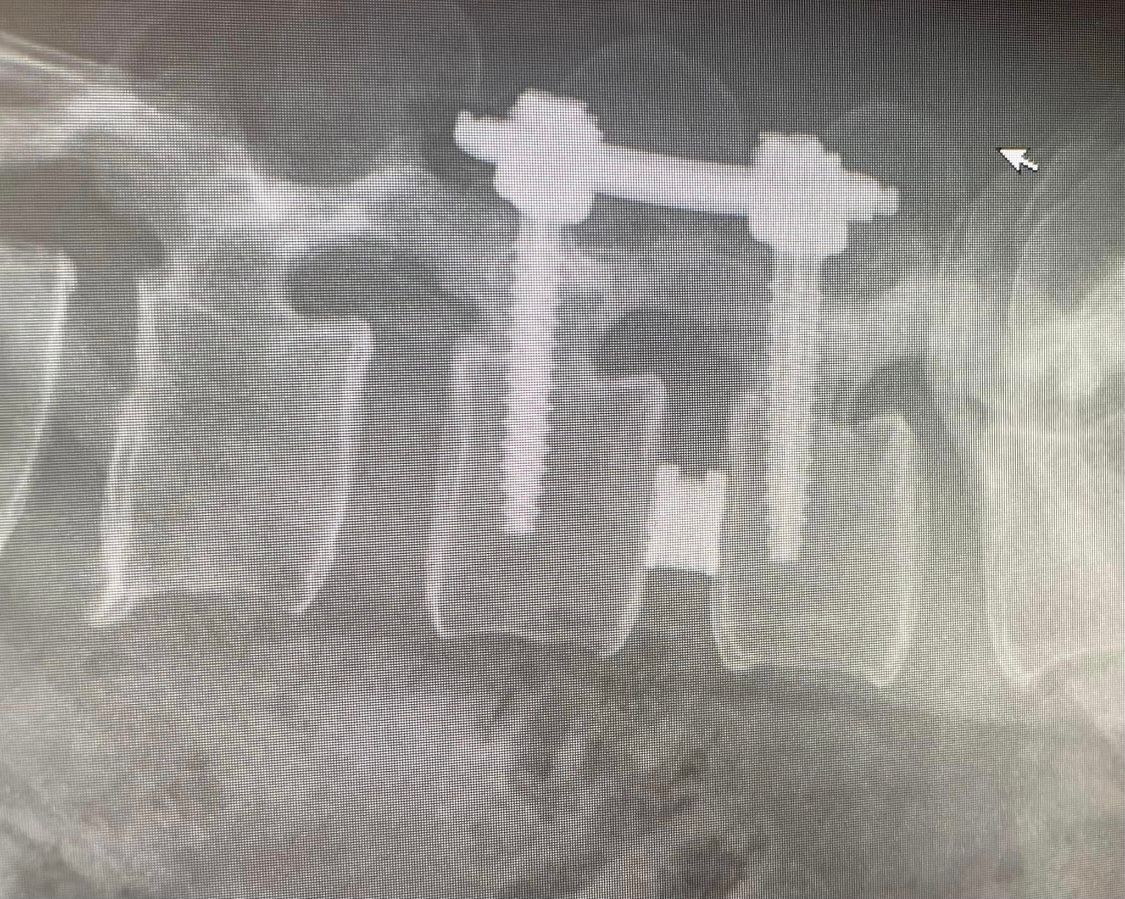

Starszy Asystent w Klinicznym Oddziale Neurochirurgicznym oraz Poradni Neurochirurgii Wojewódzkiego Szpitala Specjalistycznego im. św. Barbary nr 5 w Sosnowcu. Konsultant Kliniki Neurologii Szpitala Klinicznego nr 1 w Zabrzu. Absolwent Wydziału Lekarskiego Śląskiego Uniwersytetu Medycznego w Zabrzu. Staż podyplomowy odbył w latach 2010-2011 w Oddziale Neurochirurgii WSS nr 4 w Bytomiu. W 2018r. złożył egzamin specjalizacyjny po zakończeniu szkolenia w ramach rezydentury w WCM Opole. W 2019 roku uzyskał stopień doktora nauk medycznych. Specjalizuje się w kompleksowym leczeniu schorzeń kręgosłupa (dyskopatia, stenoza kanału kręgowego, kręgozmyk) oraz neuroonkologii. Szczególny zakres działań medycznych to nowoczesne, małoinwazyjne operacje kręgosłupa z wykorzystaniem technik endoskopowych (mikrodiscektomia - implanty rozprężalne), przezskórnych stabilizacji oraz mikrochirurgicznych dekompresji. Wykonuje procedury iniekcyjne; discoGEL, GelSTIX, kriolezje oraz blokady przeciwbólowe kręgosłupa odcinka szyjnego, lędźwiowo-krzyżowego a także stawów krzyżowo-biodrowych, które odgrywają istotną rolę w procesie diagnostyczno-leczniczym wielu zespołów bólowych. Na co dzień przeprowadza operacje w ramach kontraktu z NFZ. Członek Polskiego Towarzystwa Neurochirurgów oraz Polskiego Towarzystwa Chirurgii Kręgosłupa. Uczestnik wielu krajowych i zagranicznych kursów neurochirurgicznych, m.in. w Czechach, Słowacji, Niemczech, Włoszech, Danii, Austrii, Szwajcarii i USA. Autor licznych publikacji naukowych.

Zdjęcia i filmy